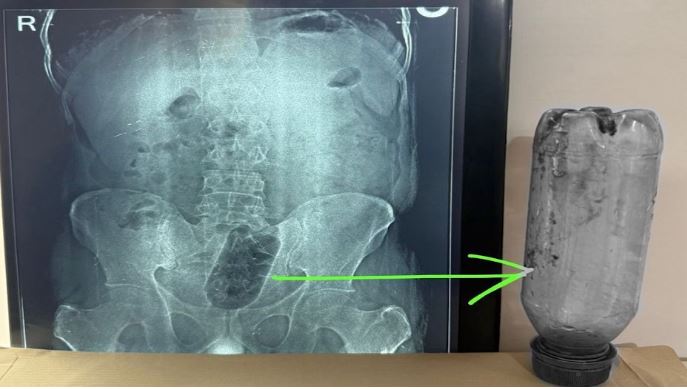

Man Undergoes Surgery in Agra to Remove Bottle Stuck in Rectum